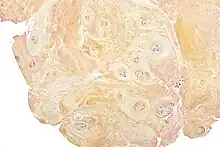

Degenerative discs typically show degenerative fibrocartilage and clusters of chondrocytes, suggestive of repair. Inflammation may or may not be present. Histologic examination of disc fragments resected for presumed DDD is routine to exclude malignancy.

Fibrocartilage replaces the gelatinous mucoid material of the nucleus pulposus as the disc changes with age. There may be splits in the anulus fibrosus, permitting herniation of elements of nucleus pulposus. There may also be shrinkage of the nucleus pulposus that produces prolapse or folding of the anulus fibrosus with secondary osteophyte formation at the margins of the adjacent vertebral body. The pathologic findings in DDD include protrusion, spondylolysis, and subluxation of vertebrae (spondylolisthesis) and spinal stenosis. It has been hypothesized that Cutibacterium acnes may play a role.[13]